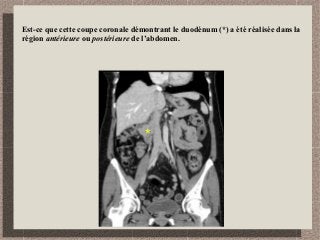

Est-ce que cette coupe coronale démontrant le duodénum (*) a été réalisée dans la

région antérieure ou postérieure de l’abdomen.

Région postérieure.

Visualisation de l’aorte et la veine cave inférieure